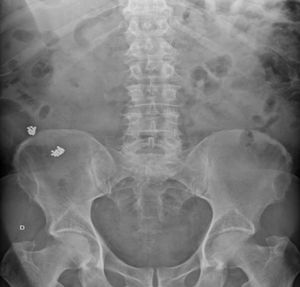

Se solicita nueva radiografía, esta vez abdominal anteroposterior, con el siguiente informe: «Cuerpos extraños metálicos en el flanco derecho, probablemente en el ciego, compatibles con restos de posta, probablemente por ingesta de carne de caza, aparentemente menos que en la radiografía de cadera previa» (fig. 1).

A los 7 meses el paciente vuelve a consultar por continuar con dolor inguinal derecho de características mecánicas, al que se sumaba un dolor sacro con la sedestación que acusaba desde hacía meses. Ante la persistencia del dolor a pesar de la analgesia se solicita radiografía de cadera. En la radiografía se aprecian imágenes radioopacas en el borde superior de la cresta iliaca derecha, descritas en el informe radiológico como «calcificaciones en palas ilíacas». Sin embargo, al observar la imagen detenidamente impresionan de objetos redondeados de menos de 2mm, que unido a la aparición de «pepitas» y la mala preparación en la colonoscopia, a pesar de que el paciente aseguró haber realizado bien los pasos previos a la prueba, generan la sospecha de presencia de cuerpos extraños en el tubo digestivo.